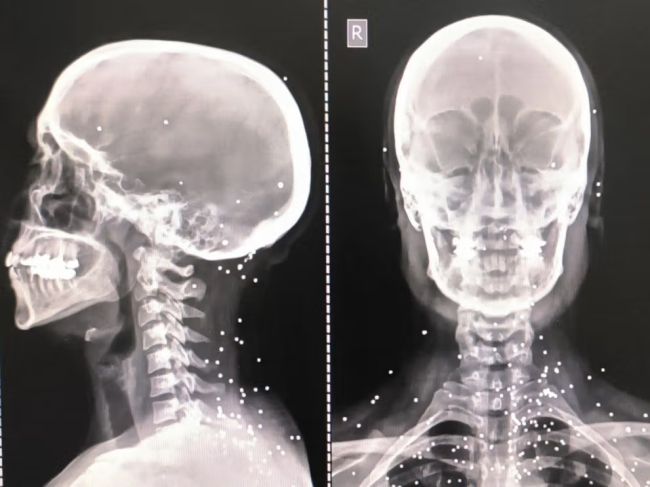

روی صورت «آناهیتا»، نقطه‌های سفید مانند یک صورت فلکی دیده می‌شود. نقاطی که در حفره‌های چشم، روی گونه و پیشانی و حتی در بخش‌هایی از مغز پراکنده‌اند. هر نقطه، یک ساچمه فلزی است که در تصاویر سی‌تی‌اسکن ثبت شده است. این ساچمه‌ها که از شاتگان شلیک می‌شوند، در فاصله نزدیک می‌توانند استخوان را خرد کرده و به‌راحتی به کره چشم نفوذ کنند.

آناهیتا که در اوایل دهه سوم زندگی خود است، دست‌کم یک چشم و احتمالا هر دو چشمش را از دست داده است.

تصویر او یکی از بیش از ۷۵ مجموعه تصویر پزشکی شامل رادیولوژی و سی‌تی‌اسکن است که از یک بیمارستان در یکی از شهرهای بزرگ ایران به دست آمده و در اختیار گاردین قرار گرفته است. تصاویری که در طول یک شب و هم‌زمان با سرکوب اعتراضات دی‌ماه ثبت شده‌اند.

تصاویر، روایتی از شدت خشونت علیه معترضان و رهگذران ارائه می‌دهند.

در یکی از تصاویر، گلوله‌ای کالیبر بالا در گردن یک جوان دیده می‌شود که باعث جابه‌جایی نای و خونریزی گسترده شده است.

در پرونده‌ای دیگر، گلوله‌ای در مغز یک بیمار باقی مانده و وجود حباب در جمجمه، نشانه‌ای از آسیب شدید مغزی است. آسیبی که کارشناسان آن را با احتمال پایین بقا توصیف کرده‌اند.

در تصاویر دیگر نیز گلوله‌هایی در نزدیکی ستون فقرات یا مسیرهای مشخص تخریب بافت و استخوان دیده می‌شود.

گاردین در گزارش خود تاکید کرد که در برخی تصاویر، تنها یک یا دو ساچمه در جمجمه دیده می‌شود که پس از عبور از چشم در حفره آن متوقف شده‌اند.

در موارد دیگر، صدها ساچمه در بدن پراکنده شده و بافت نرم را تخریب کرده‌اند.